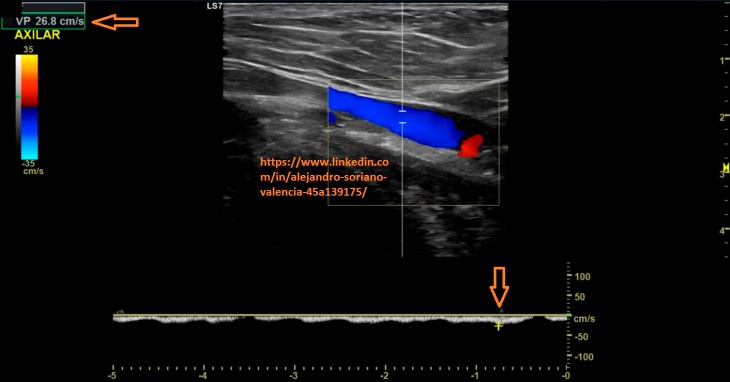

o Axilar.

5. Axilar transversal.

6. Axilar longitudinal. Estudio triplex.